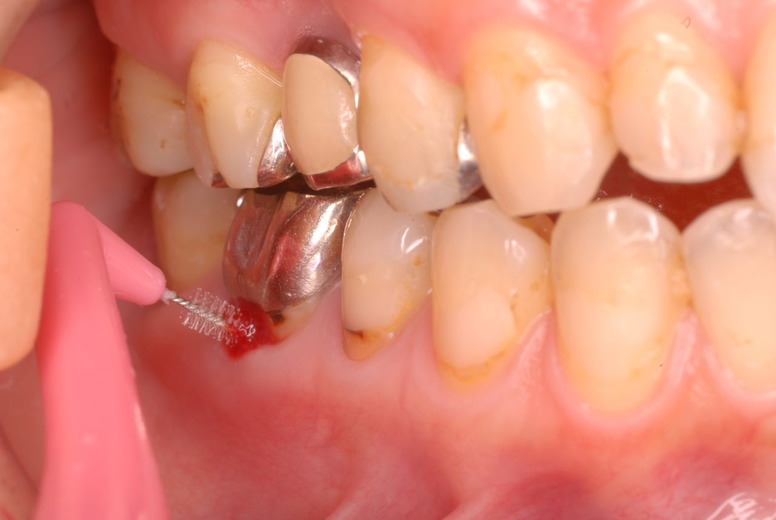

写真左下の親知らずが痛くなり抜歯しました。その後歯茎を除去して虫歯を露出させる処置を二回ほどしています。

レントゲンでは小さいですが、こう言う虫歯が一番怖いのです。

治療の成功率は極めて悪くすぐ再発しやすいのです。

隣の14歳大臼歯がひどい虫歯になり治療不可能になりつつある状態のレントゲン